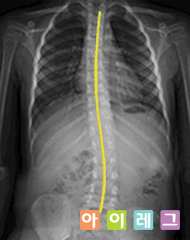

정상적인 척추와는 달리 전반적인 척추가 'S' 자나 'C' 자 모양으로 휘어지고 , 동시에 척추 마디마디가 회전하여 틀어지는 형태로 , 단순하게 비틀어진 변형이 아니라 회전과 더불어 입체적으로 변형된 상태을 말합니다 .

척추즉만증은 서서히 진행되기 때문에 대개 잘 모르고 지내다가 변형이 상당히 진행되어 등이 옆으로 구부러지고 , 어깨 또는 골반의 높이가 달라지거나 , 한쪽 견갑골이나 둔부가 돌출된 것을 우연히 발견하고 내원하는 경우가 많이 있습니다 .

대부분 10 세 전후에 시작되어 특히 여아들에게 심하게 나타날 수 있고 , 키가 크는 동안 계속 진행됩니다 . 한번 휘어진 척추는 성장기 동안 키가 크면서 그 각도가 점점 심해지게 되는데 발병 초기에 정확한 검진으로 30~40 도 이상의 악성 측만증으로 휘어지는 변형을 막는데 초점을 맞추어야 합니다 . |